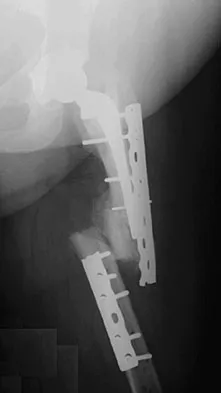

Figures 7a and 7b show the radiographs of a 51-year-old woman who injured her left leg after falling off a stepladder. Surgical reconstruction is performed with a compression screw and side plate; the postoperative radiograph is shown in Figure 7c. Following gradual progression of weight bearing, she reports that she slipped again and placed full weight on the extremity. She now notes a new onset of increased pain in her left thigh and hip region. Follow-up radiographs are shown in Figures 7d and 7e. Reconstruction should consist of

The initial fracture was an unstable reverse oblique intertrochanteric fracture with subtrochanteric extension. Initial fixation with a high-angled screw and side plate construct may not provide stability as well as a 95 degree fixed-angle device or a intramedullary hip screw device. The follow-up radiographs show loss of fixation and further propagation of the fracture distally. Reconstruction would best be accomplished with hardware removal and conversion to a long intramedullary nail with femoral head fixation or a 95 degree angled plate and screw device. Conversion to a longer plate does not improve the biomechanical situation at the primary fracture site. In situ bone grafting would not provide any additional stability and would not correct the deformity. The proximal femoral fracture is not amenable to retrograde nailing. Cerclage wiring will not sufficiently enhance stability and is not indicated. Bridle SH, Patel AD, Bircher M, Calvert PT: Fixation of intertrochanteric fractures of the femur: A randomized prospective comparison of a gamma nail and dynamic hip screw. J Bone Joint Surg Br 1991;73:330-334. DeLee JC: Fractures and dislocations of the hip, in Rockwood CA Jr, Green DP, Bucholz RW, Heckman JD (eds): Rockwood and Green's Fractures in Adults, ed 4. Philadelphia, PA, Lippincott-Raven, 1996, pp 1659-1825. Haidukewych GJ, Israel TA, Berry DJ: Reverse obliquity fractures of the intertrochanteric region of the femur. J Bone Joint Surg Am 2001;83:643-650.

- Sanders RW, Regazzoni P: Treatment of subtrochanteric femur fractures using the dynamic condylar screw. J Orthop Trauma 1989;3:206-213.